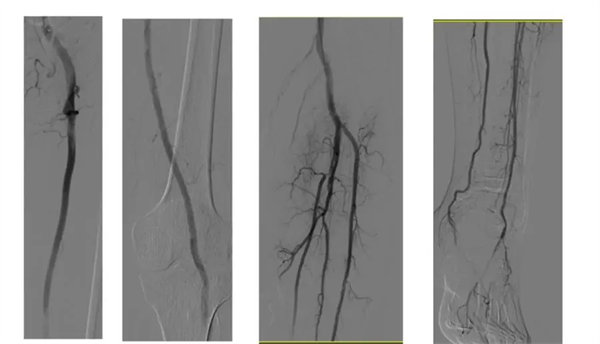

再次行“左下肢動脈造影術”提示:左側髂外動脈、股淺動脈、腘動脈完全再通,膝下動脈基本開通,左側足底、左側足背動脈弓基本完全顯影,左下肢動脈血運基本完全重建,患者左下肢缺血癥狀明顯緩解,術后患者恢復良好,治愈出院。